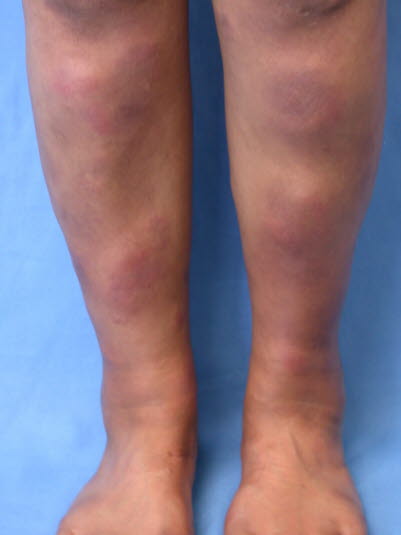

Rumień guzowaty

- Rumień guzowaty jest stanem zapalnym podskórnej tkanki tłuszczowej, związanym z sarkoidozą i zwykle z gruźlicą, ale może być również spowodowany wieloma innymi zakażeniami.1,19

- Zapalenie jest zwykle poprzedzone gorączką, uczuciem zmęczenia i bólem stawów.

Rumień guzowaty - Zwykle w tkance podskórnej występuje kilka charakterystycznych rumieniowych, purpurowych, tkliwych, nieostro odgraniczonych, lekko uniesionych nacieków o średnicy 1–6 cm.19

- Miejsca predylekcyjne to w szczególności podudzia, ale zajęte mogą być również kostki, uda lub przedramiona.19